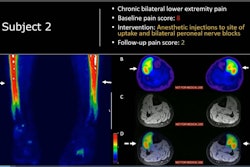

Adult male with decades of right neck pain, discomfort, and tightening following birth injury. The patient had failed multiple standard therapeutic maneuvers before presenting for F-18 FDG PET/MRI. Images show abnormally elevated FDG uptake (white arrows; SUVmax = 1.2) observed in a linear pattern in the space in the posterolateral right neck, between the oblique capitis inferior and the semispinalis capitis muscles, where the greater occipital nerve resides. By comparison, the same region on the contralateral, asymptomatic side of the neck has an SUVmax = 0.7. This result encouraged a surgeon to explore the area. The surgeon ultimately found a collection of small arteries wrapped around the nerve in this location. The small arteries underwent lysis by the surgeon and the patient reported tremendous relief of symptoms. (A) Coronal thick slab MIP [maximum intensity projection] of F-18 FDG PET. (B) Axial LAVA [Dixon liver acquisition with volume acquisition] Flex MRI through the cervical spine. (C) Axial PET at the same slice as the axial MRI. (D) Fused axial PET/MRI. Image courtesy of Peter Cipriano of Stanford University; caption courtesy of SNMMI.The study suggests that this PET/MRI combination could be an effective way for those who experience chronic pain to get relief, Biswal said in the society statement.